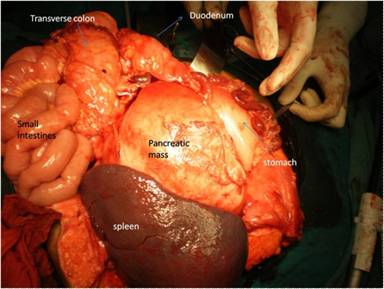

A 35-year-old female presented with dull aching pain and lump in central abdomen gradually increasing in size for last two years. Patient had no history of vomiting, fever, jaundice, anorexia and weight loss. There was no history suggestive of previous episode of acute pancreatitis. On abdominal examination, a 13x16 cm nontender, firm, retroperitoneal lump was palpable in the epigastrium, left hypochondrium and umbilical region along with splenomegaly. CECT of the abdomen demonstrated well defined 15x15 cm solid mass arising from body and tail of pancreas with splenomegaly (Figure 1). Splenic vessels were encased by the mass. The head of the pancreas was normal. The mass was free from stomach and it was not involving the superior mesenteric vessels. There was no lymphadenopathy or free fluid. With a suspicion of benign tumor of the pancreas patient was planned for distal pancreatectomy with splenectomy. Intra-operatively there was a 15x15 cm firm mass was found to be arising from the body and tail of the pancreas (Figure 2). The mass was completely resected by performing distal pancreatectomy and splenectomy. Postoperative period of the patient was uneventful and she was discharged on postoperative day nine.

Figure 2. Intra-operative picture of pancreatic mass. |